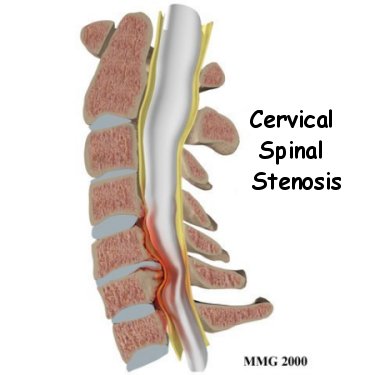

The spinal cord is a column of nerve tissue protected by a bony tube in the spinal column. Conditions that narrow the space in this tube put the spinal cord at risk of getting squeezed. This narrowing in the spinal column of the neck is called cervical spinal stenosis, or cervical stenosis. Pressure against the spinal cord as a result of spinal stenosis causes myelopathy, a condition that demands medical attention. Myelopathy can cause problems with the bowels and bladder, change the way you walk, and affect your ability to use your fingers and hands.

The bony spinal canal normally has more than enough room for the spinal cord. Typically, the canal is 17 to 18 millimeters around, slightly less than the size of a penny. Spinal stenosis occurs when the canal narrows to 13 millimeters or less. When the size drops to 10 millimeters, severe symptoms of myelopathy occur. Myelopathy is a term for any condition that affects the spinal cord. The symptoms of myelopathy result from pressure against the spinal cord and reduced blood supply in the spinal cord as a result of the pressure.

Some people are born with a spinal canal that is narrower than normal. This is called congenital stenosis. They may not feel problems early in life, but having a narrow canal to begin with places them at risk for stenosis. Even a minor neck injury can set them up to have pressure against the spinal cord. People born with a narrow spinal canal often have problems later in life, because the canal tends to become narrower due to the affects of aging. These degenerative changes often involve the formation of bone spurs (small bony projections) that point into the spinal canal and put pressure on the spinal cord.

Degeneration is the most common cause of spinal stenosis. Wear and tear on the spine from aging and from repeated stress and strain can cause many problems in the cervical spine. The intervertebral disc can begin to collapse, shrinking the space between vertebrae. Bone spurs may form that protrude into the spinal canal and reduce the space available to the spinal cord. The ligaments that hold the vertebrae together may become thicker and can also push into the spinal canal. All of these conditions narrow the spinal canal.

Degeneration is the most common cause of spinal stenosis. Wear and tear on the spine from aging and from repeated stress and strain can cause many problems in the cervical spine. The intervertebral disc can begin to collapse, shrinking the space between vertebrae. Bone spurs may form that protrude into the spinal canal and reduce the space available to the spinal cord. The ligaments that hold the vertebrae together may become thicker and can also push into the spinal canal. All of these conditions narrow the spinal canal.